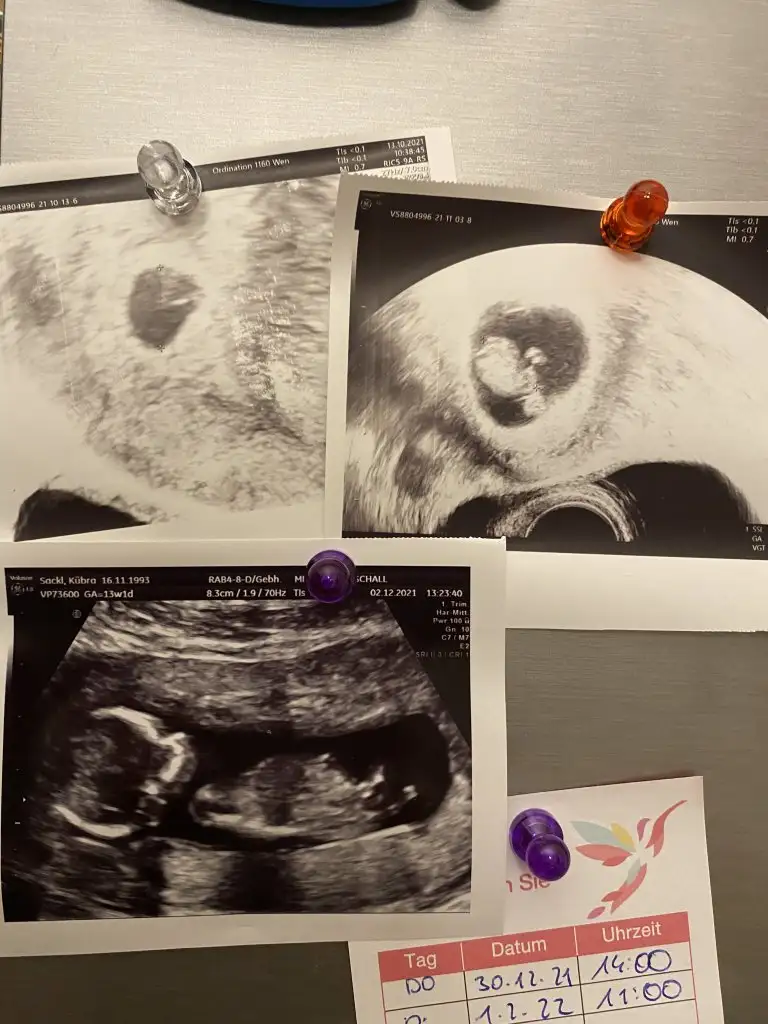

Kızlar şaka maka 2. Trimester a girdik valla keseydi kalp atışıydı derken öyle böyle geçti zaman… duygu durumlarınız nasıl? Ben acayip heyecanlıyım bu da benim miniğin bir noktadan evrimi